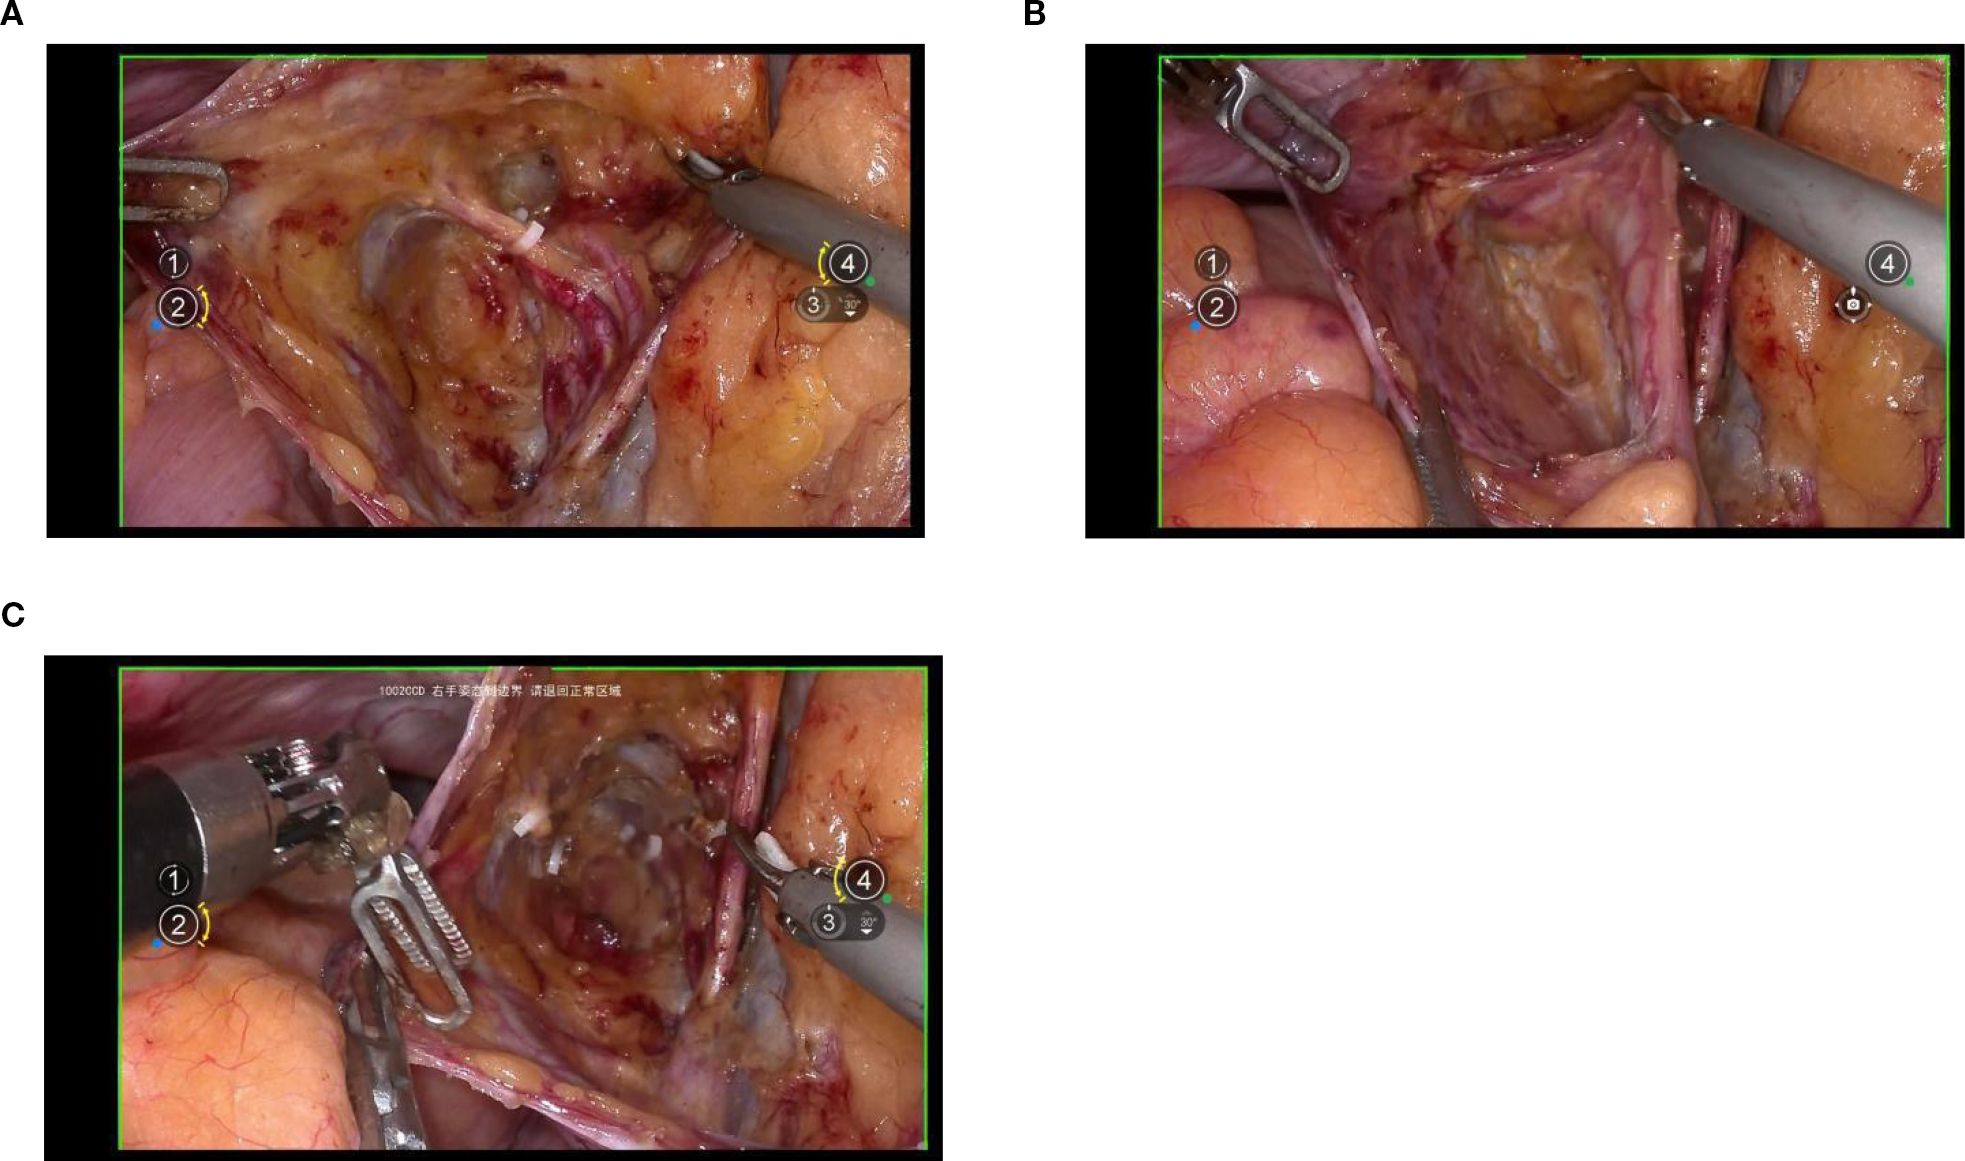

Exposure of the lateral parametrium is primarily achieved by separating the paravesical space, Latzko’s pararectal space, and Okabayashi’s pararectal space. This allows for the dissection of the ureteric embryonic compartment, the mesorectum of the hindgut embryonic compartment (lateral rectal wall), the posterior lateral bladder wall of the urogenital embryonic compartment, and the mesometrial outlet of the Müllerian embryonic compartment. Following vascular clamping between the Latzko’s pararectal and paravesical spaces, the uterine artery, superficial uterine vein, and deep uterine vein are sharply dissected. (Figures 4A-C).

Figure 4. (A, B) shows the separation of the ureteric embryonic compartment, hindgut embryonic compartment, urogenital embryonic compartment, and Müllerian embryonic compartment by opening the paravesical space, Latzko’s pararectal space, and Okabayashi’s pararectal space; (C) shows the cut ends of the uterine artery and the deep uterine vein.

4.5 Dorsal parametrium

Exposure of the dorsal parametrium is achieved by opening the membrane bridge (15–17) between the rectum of the hindgut embryonic compartment, the posterior vaginal wall of the Müllerian embryonic compartment, and the sacral ligaments. This allows access to the rectovaginal space, facilitating the separation of the hindgut embryonic compartment from the Müllerian embryonic compartment. The sacral ligaments should be sharply dissected at the level of the sacral fascia. Figures 5A-C.

Figure 5. (A) shows the membranous bridge between the hindgut embryonic compartment and the Müllerian embryonic compartment; (B) shows the separation of the hindgut embryonic compartment and the Müllerian embryonic compartment; (C) shows the transection of right uterosacral ligament.